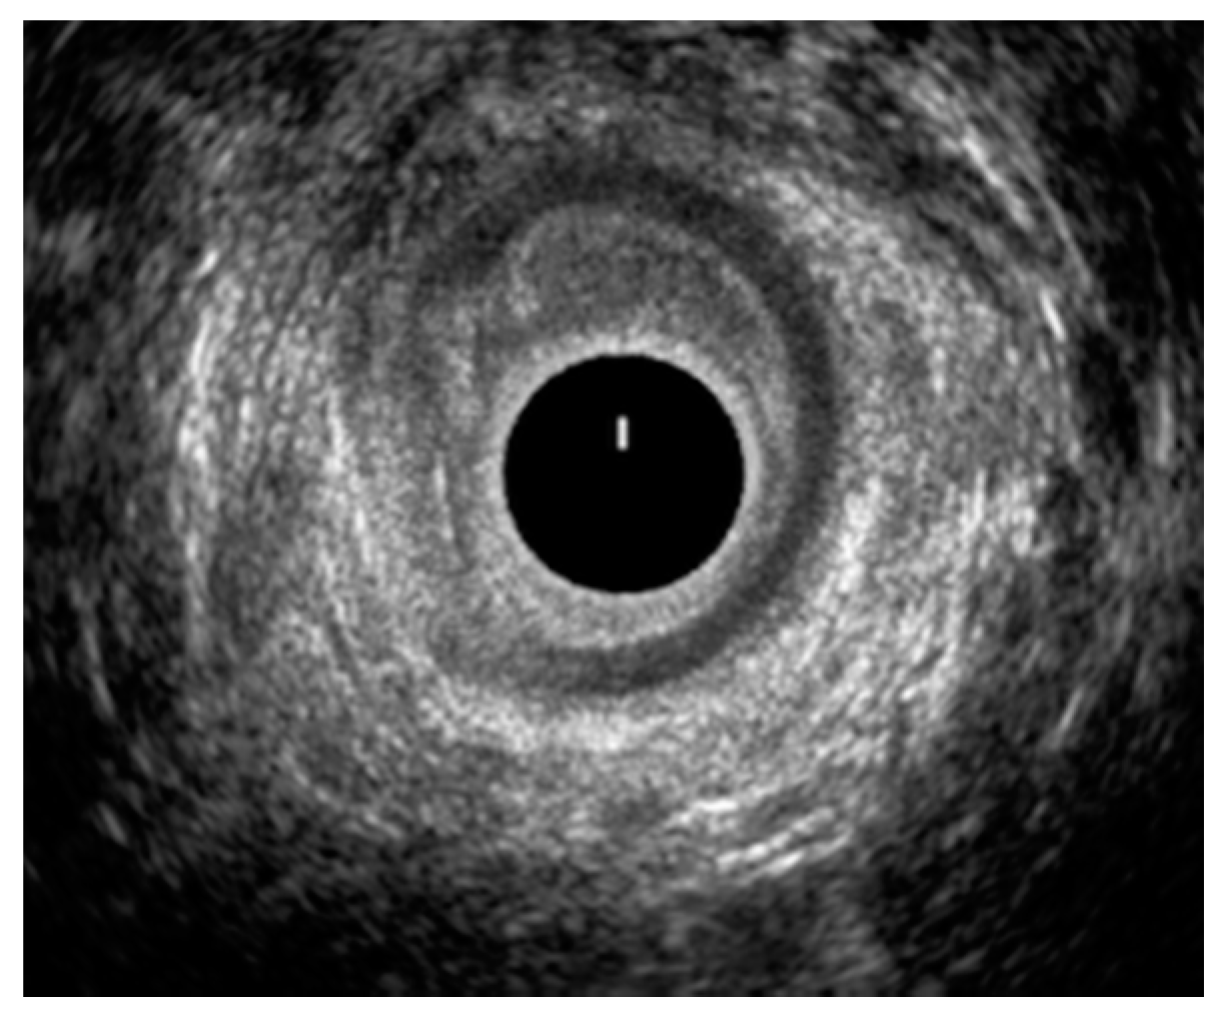

3.3. High-Resolution Anorectal Manometry and Balloon Expulsion Test